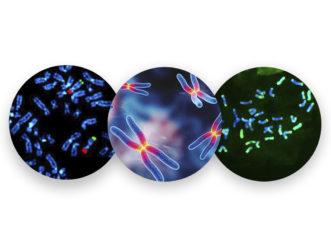

Nuestros Estudios

En H&E Diagnostics contamos con tecnología de última generación y personal altamente capacitado para el diagnóstico y entrega oportuna de resultados ofreciendo los siguientes servicios especializados: